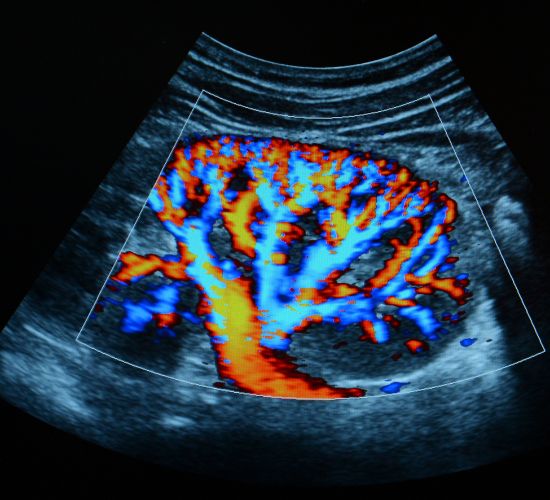

سونوگرافی کالرداپلر پستان: این تکنیک برای ارزیابی جریان خون در ناحیه پستان به‌کار می‌رود و به شناسایی مشکلات عروقی و بررسی وضعیت توده‌ها یا کیست‌ها کمک می‌کند.

سونوگرافی کالرداپلر پستان